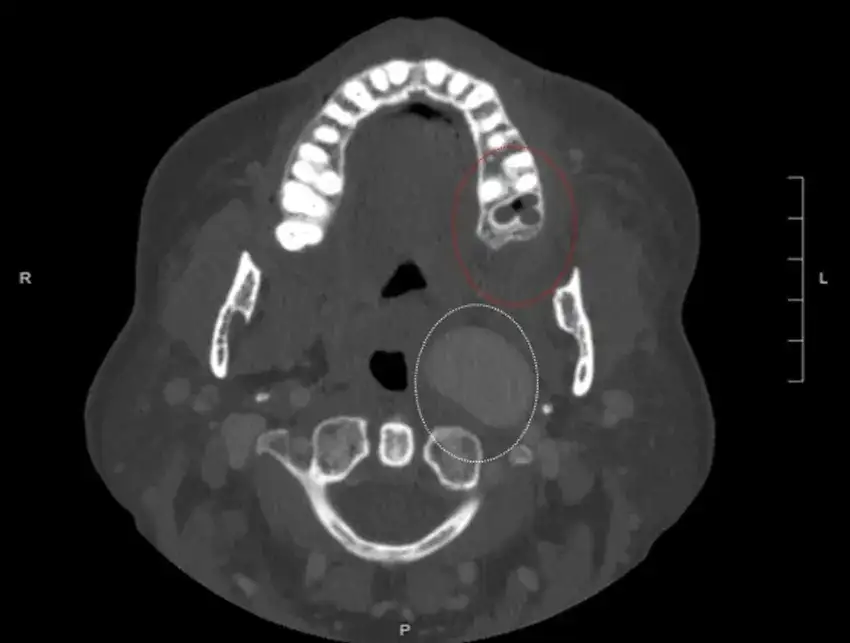

Badania kliniczne i radiologiczne w diagnostyce

W diagnostyce ropnia mózgu kluczowe są różne metody badawcze, które pozwalają na dokładne określenie obecności infekcji. Badania kliniczne obejmują szczegółowy wywiad lekarski oraz badanie neurologiczne, które pomagają w ocenie stanu pacjenta. Z kolei techniki obrazowania, takie jak rezonans magnetyczny (MRI) oraz tomografia komputerowa (CT), są niezbędne do wizualizacji zmian w mózgu. Te badania nie tylko umożliwiają zobaczenie ewentualnych ropni, ale również pomagają w ocenie ich lokalizacji oraz wielkości, co jest kluczowe dla dalszego postępowania.

Warto podkreślić, że wybór odpowiedniej metody diagnostycznej zależy od stanu pacjenta oraz dostępnych technologii. MRI jest szczególnie przydatne w identyfikacji zmian w tkance mózgowej, podczas gdy CT może być szybszą metodą w sytuacjach nagłych. Obie techniki mają swoje zalety i ograniczenia, dlatego lekarze często stosują je komplementarnie, aby uzyskać pełniejszy obraz stanu zdrowia pacjenta.